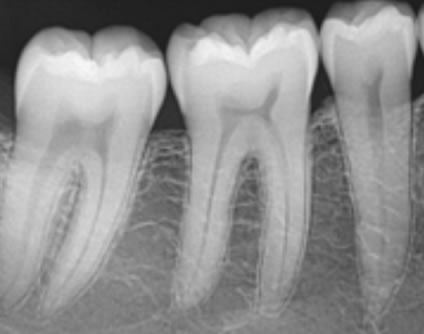

Pojedinačna snimka zuba - (intraoralna snimka) - Snimka prikazuje detaljnije i preciznije stanje zuba i okolne kosti.

Pojedinačna snimka zuba - (intraoralna snimka) - Snimka prikazuje detaljnije i preciznije stanje zuba i okolne kosti.

Koristimo je uvijek za precizniju dijagnostiku patoloških stanja zuba i okolne kosti te nakon liječenja zuba.

Bitewing snimka zubi - To je snimka stražnjih gornjih i donjih zuba, koristi se za detekciju početnog karijesa između stražnjih zubi.

Bitewing snimka zubi - To je snimka stražnjih gornjih i donjih zuba, koristi se za detekciju početnog karijesa između stražnjih zubi.

Početni karijes između zubi se teško dijagnosticira prilikom kliničkog pregleda pa je preporučljivo napraviti ovu snimku za detekciju karijesa.